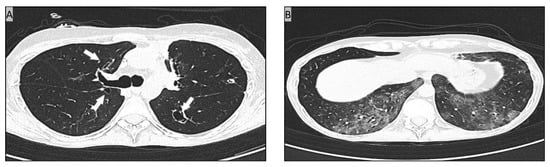

2. Case Report